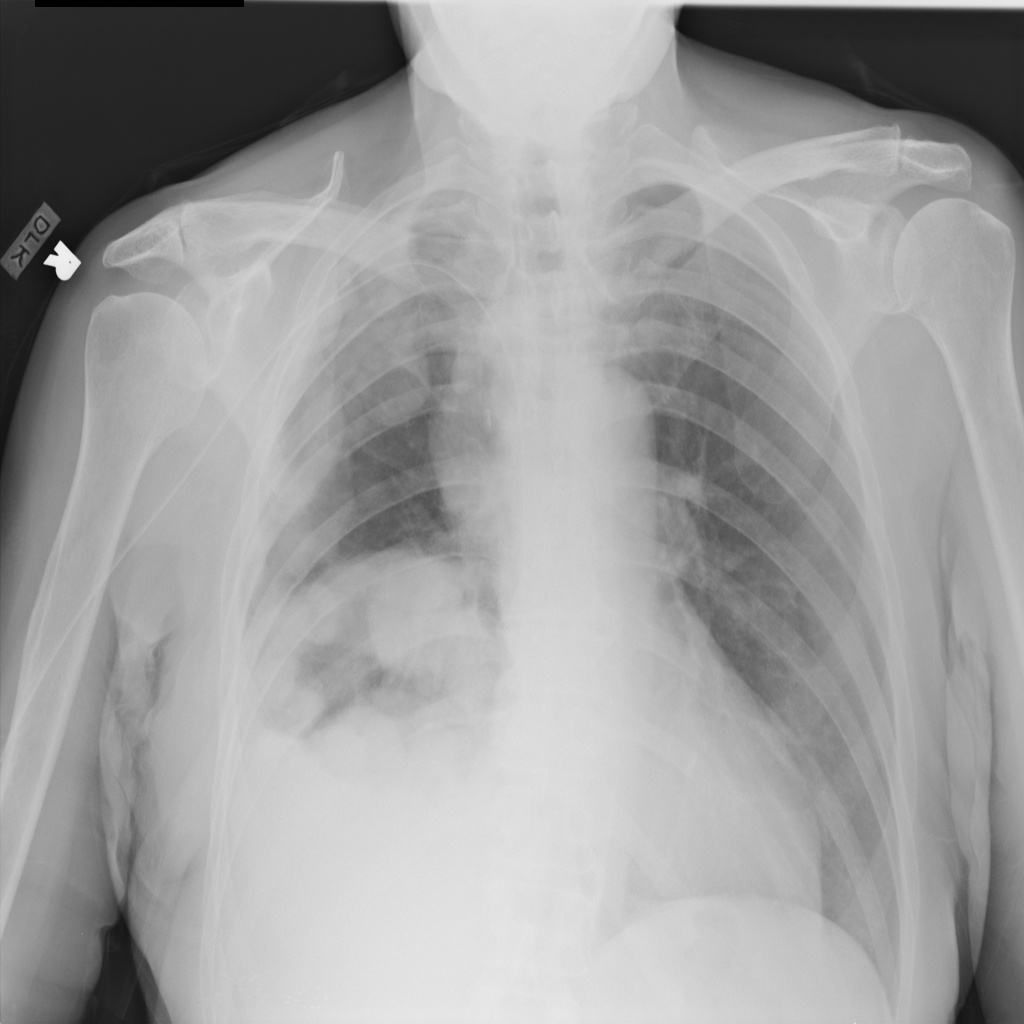

Mass

A mass is a larger focal opacity or lesion seen on the image. It is a descriptive finding that can have several causes and usually needs more imaging or clinical context to characterize.

PAT-4639 · IMG-024Mass

PAT-4639 · IMG-024

AP